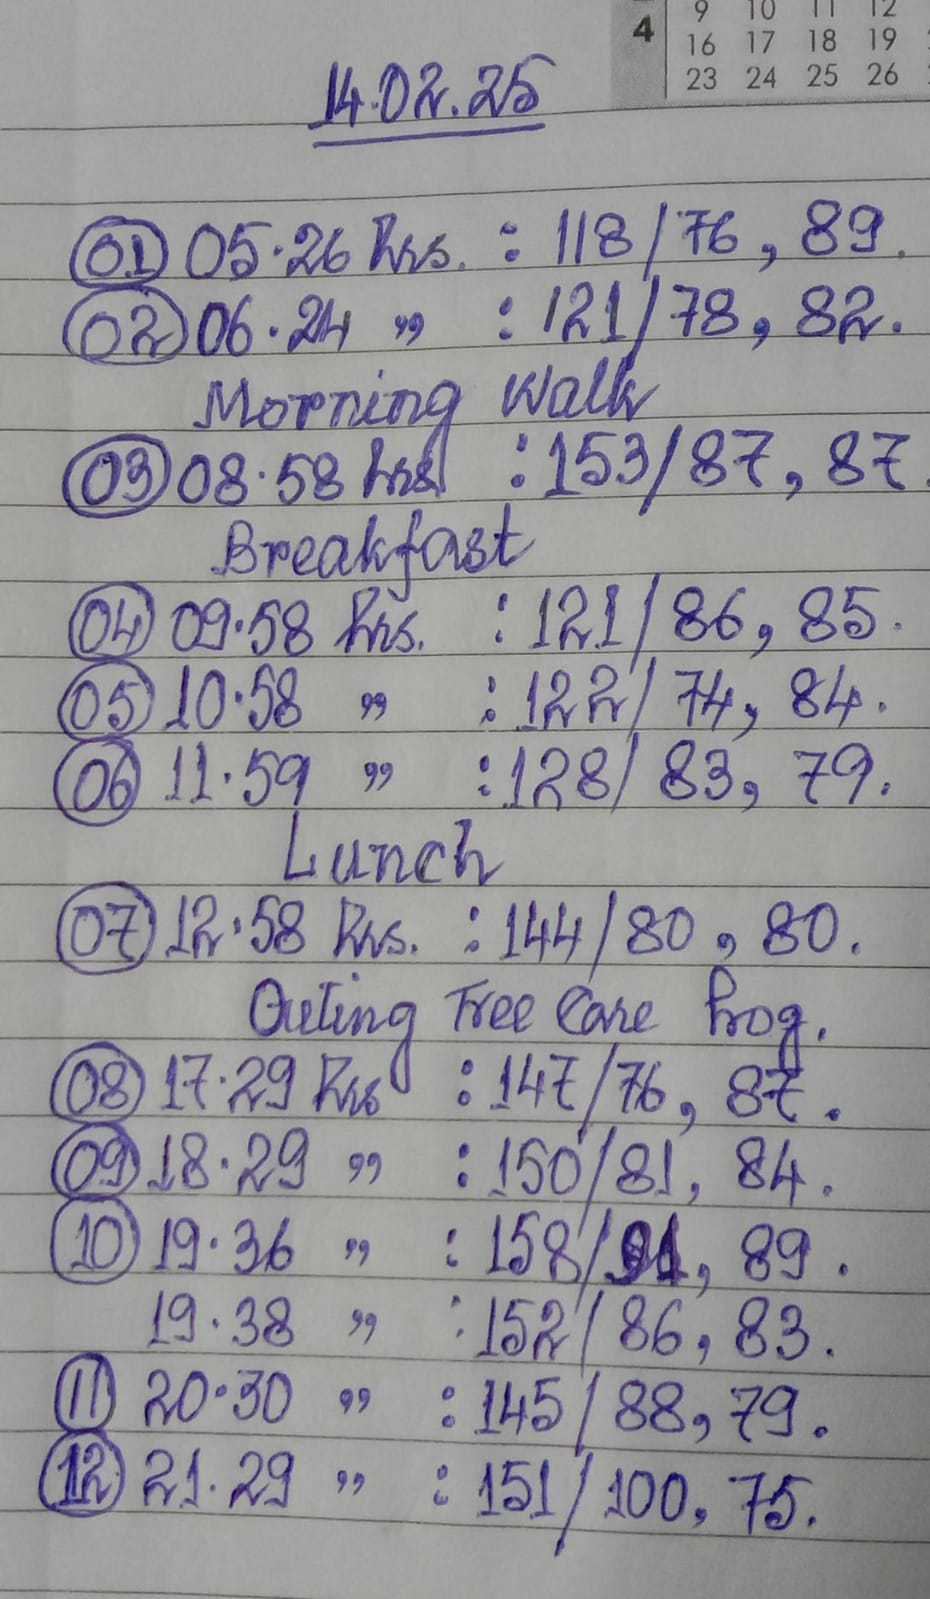

[8/9, 10:50 AM] PaJR PHR Moderator: Today's update: Traction applied for the right femur post nail removal with continued intermittent physiotherapy to relieve the right knee fixed flexion contractures

[8/12, 2:58 PM] PaJR PHR Moderator: On Saturday afternoon patient had severe cough and shortness of breath after eating bread soaked in milk following which he became hypoxic and was shifted to AMC.

Currently respiratory rate 30 per minute

SpO2 93% at 2 litres of oxygen

Sensorium unresponsive

No spontaneous eye opening

Dolls eye normal and inducing wakefulness

Last he made eye contact with his wife was yesterday

[8/12, 2:59 PM] PaJR PHR Moderator: Saturation falling to 86% on room air